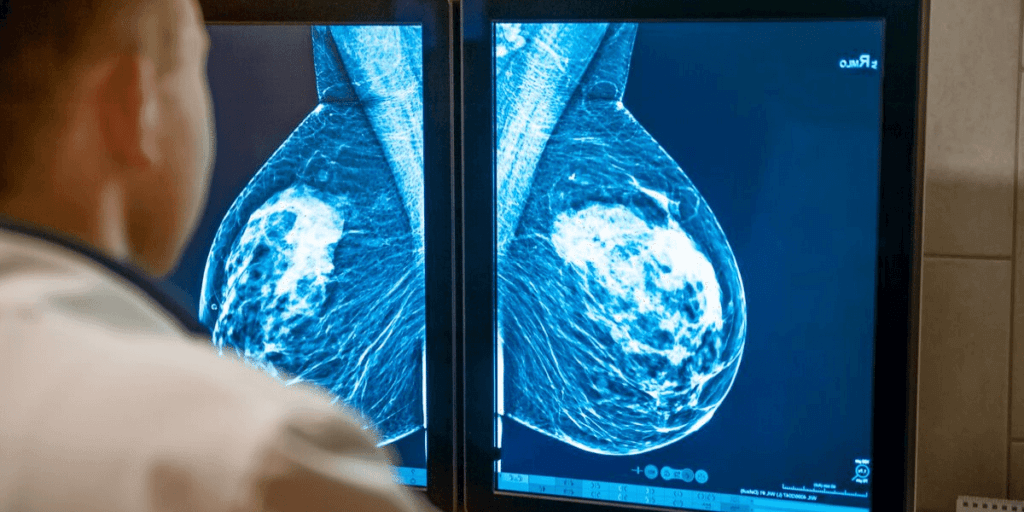

Breasts contain glandular, connective and fat tissue. Dense breast tissue contains milk glands, milk ducts and supportive tissue. Non dense tissue contains fatty tissue. On a mammogram, nondense breast tissue appears dark and transparent, while dense breast tissue appears more solid and white, which makes it difficult to see through.

Dense breast tissue cannot be felt in a clinical breast exam or in a breast self-exam, it can only be  seen on a mammogram. Once you have your mammogram completed, the radiologist who  interprets the mammogram will determine the ratio of nondense tissue and dense tissue, and will assign a level of breast density. The radiologist typically will use a results reporting system called Breast Imaging Reporting and Data System (BI-RADS). The levels of density are divided into four categories: